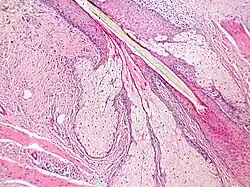

Lidská mazová žláza je alveolus (váček) obklopený na obvodu plochými buňkami bohatými na ribozomy. Tyto buňky se množí a postupně se dostávají do střední části alveolu, kde se plní tukovými kapénkami a postupně odumírají. Z těchto odumřelých buněk vzniká kožní maz. Ten se dostává díky stahům hladkých svalů (arrector pili) do vlasového folikulu a odtud na povrch pokožky. Výživný kožní maz je jedním z důvodů pro vznik zánětů folikulu (folikulitid) a akné.[4]